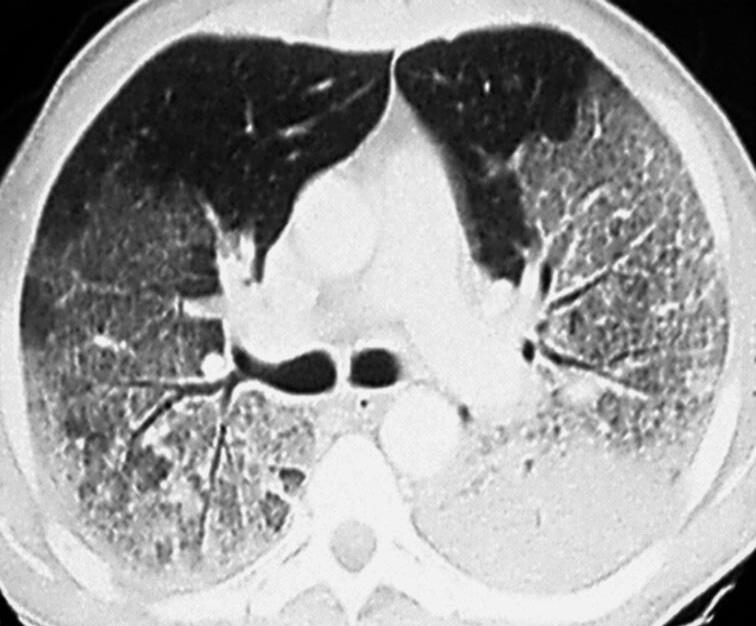

28 Síndrome da Angústia Respiratória Aguda – Posição Prona e Oxigenação por Membrana Extracorporal, 251

Alexandre Marini Isola  Diogo Toledo  Flávia J. A. Pfeilsticker